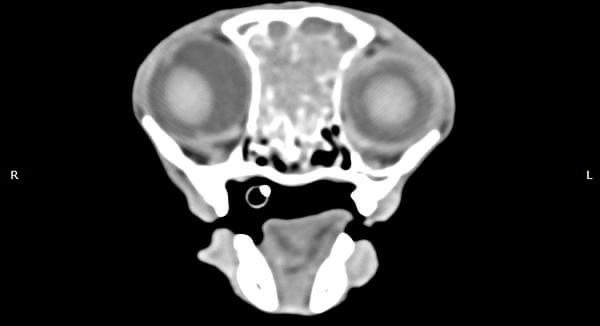

貓咪 鼻腔腫瘤腺癌 Adenocarcinoma

鼻腔腫瘤的診斷需要仰賴電腦斷層掃瞄定位病灶處,同時使用鼻腔內視鏡探查、採樣才能確診,同時有這兩項設備的醫院並不多,所以臨床事並不是那麼容易確診。貓咪幾個月前開始打噴嚏、流鼻、鼻塞越來越嚴重,他院住院治療改善不佳後轉診至築心檢查。

狗狗 鼻腔腫瘤 惡性上皮癌

鼻腔腫瘤的診斷需要仰賴電腦斷層掃瞄定位病灶處,同時使用鼻腔內視鏡探查、採樣才能確診,同時有這兩項設備的醫院並不多,所以臨床上並不是那麼容易確診。狗狗的慢性鼻炎維持3-4個月,越來越嚴重,他院轉診至築心,經由內視鏡+電腦斷層確認為鼻腔上皮癌,而且由於病程時間長,已經轉移至胸腔,代表壽命不長了,至少家人心中有個答案,有心理準備陪狗狗最後一段路。

狗狗 鼻腔腫瘤 淋巴癌

鼻腔腫瘤的診斷需要仰賴電腦斷層掃瞄定位病灶處,同時使用鼻腔內視鏡探查、採樣才能確診,同時有這兩項設備的醫院並不多,所以臨床事並不是那麼容易確診。狗狗如果有打噴嚏、鼻分泌物 鼻塞,對藥物治療反應不好, 就還是要做進一步檢查才會比較安心唷!

鼻上皮細胞癌

鼻腔症狀是門診中狗貓最常見的主訴之一,但在診斷上卻不那麼容易,在缺乏如電腦斷層、內視鏡、牙科X光等特定設備的情況下,門診醫師多只能嘗試性的給藥觀察,對於慢性、頑固、難治的鼻腔問題往往便束手無策了。

柴犬皮皮因長期有鼻塞、流鼻血、流鼻水的症狀來築心就診,在這之前已經換過兩間醫院,但治療效果都不太好。在一系列的評估後,我們為皮皮安排了電腦斷層以及鼻腔內視鏡的檢查,檢查後發現在皮皮的鼻腔內有疑似腫瘤的團塊,並且向後侵入鼻竇,甚至已經接近大腦。我們運用內視鏡設備採樣取得了團塊的切片,並得到鼻上皮細胞癌的診斷。